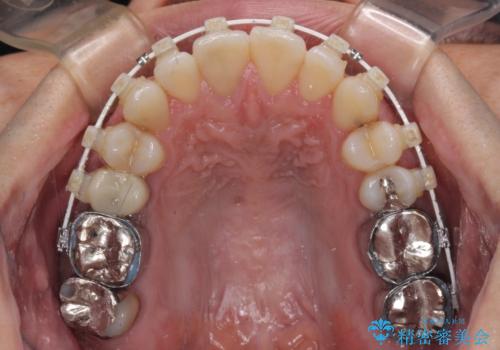

受け口傾向の咬み合わせ 前歯のデコボコをワイヤー矯正で素早く改善

- 審美装置

ワイヤー矯正でもマウスピース矯正でも対応可能とお伝えし、非常に悩まれていましたが、2年後に転勤の可能性が高いとのことで、治療終了までの期間を想定しやすいワイヤー矯正にて治療を行うこととしました。

前歯のクロスバイトは、改善の途中で歯髄壊死を起こすリスクが高くなるため、マウスピース矯正よりもワイヤー矯正をお勧めしております。

この患者様もクロスバイトはあっという間に改善され、1年強で速やかに治療を終えることができました。